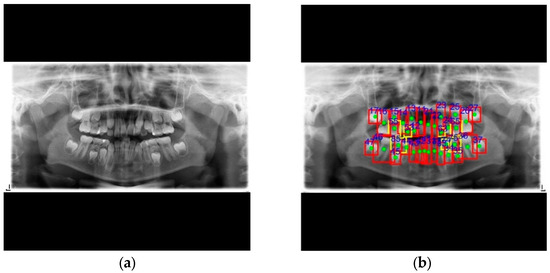

| PANO | Precision ↑ | 96.2% | 88.7% | 98.3% | 95.7% | 70.8% | 49.6% | 97.0% | 93.1% |

| Recall ↑ | 98.6% | 93.5% | 99.4% | 97.8% | 65.3% | 28.1% | 99.2% | 96.5% | |

| PA | Precision ↑ | 96.5% | 99.5% | 83.8% | |||||

| Recall ↑ | 92.6% | 95.6% | 95.4% | ||||||

| BW | Precision ↑ | 95.7% | 99.0% | 96.8% | |||||

| Recall ↑ | 98.5% | 99.8% | 99.6% | ||||||